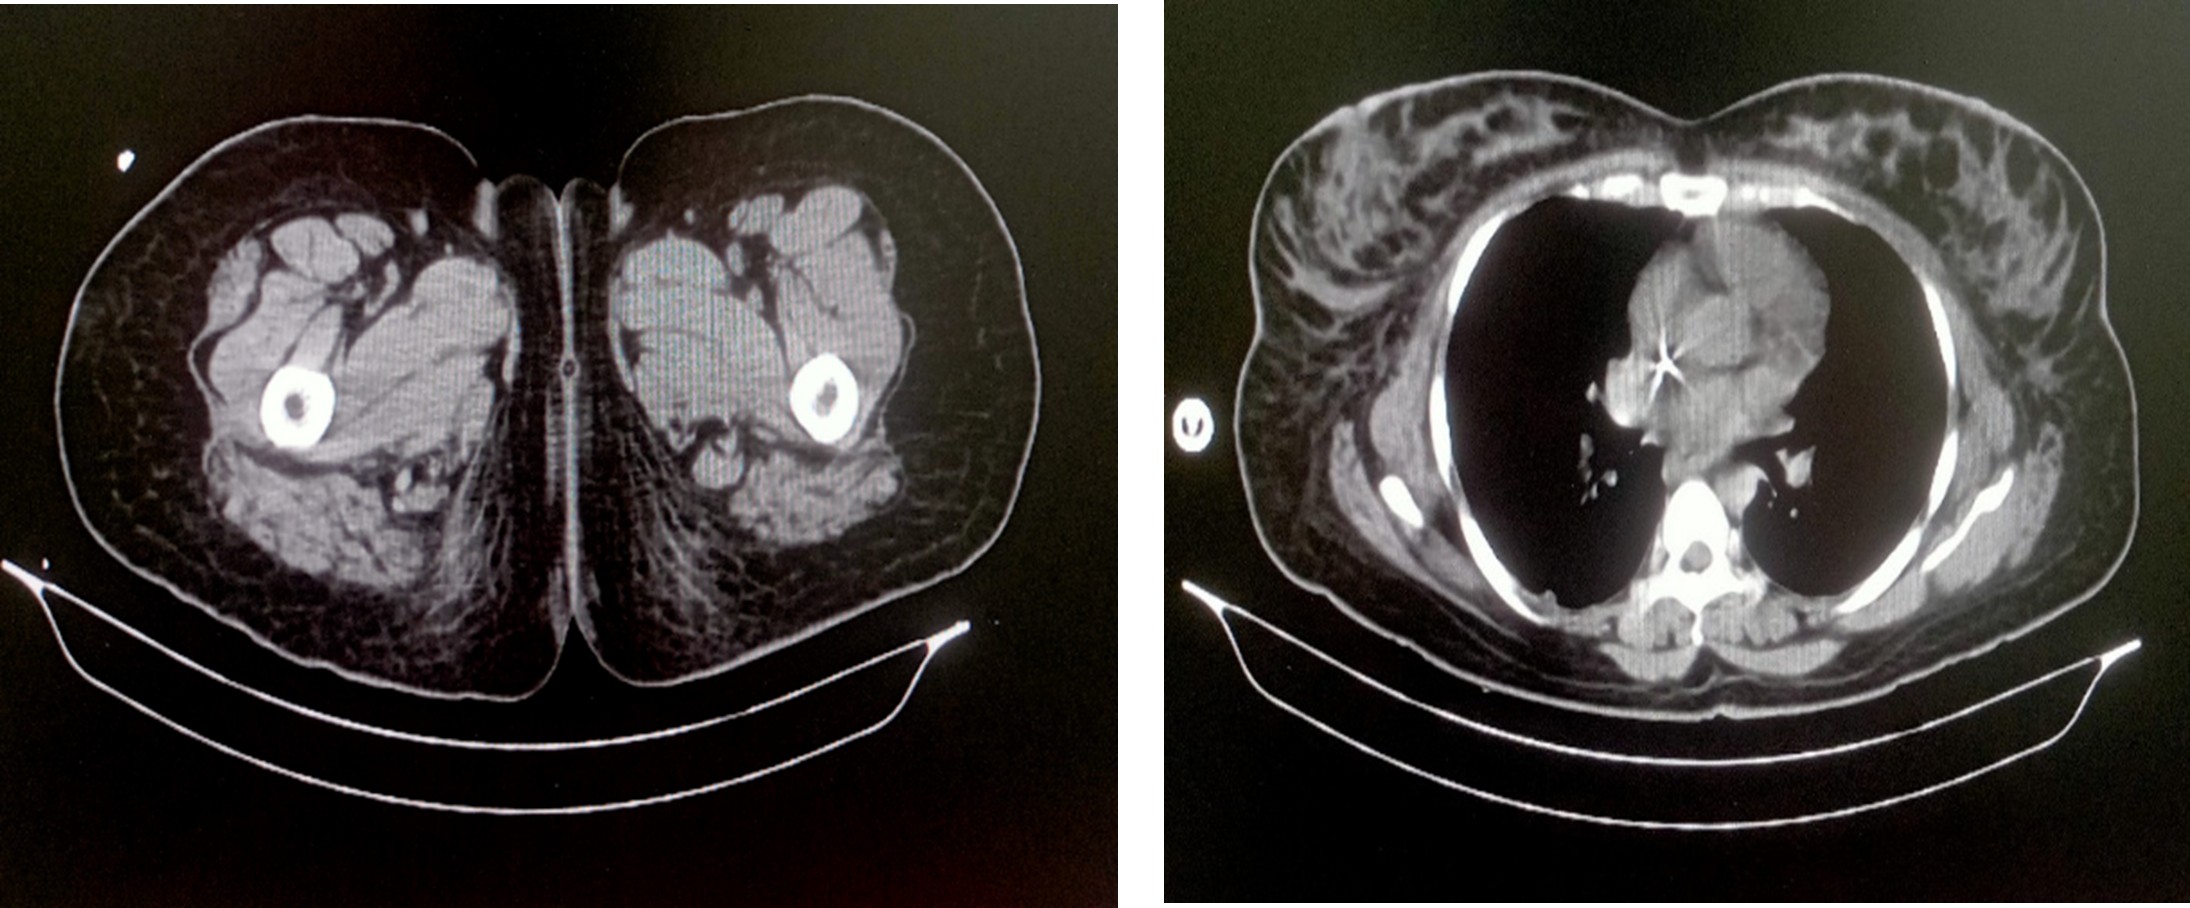

Multislice CECT -Abdomen and pelvis (06.02.2026)

A case of post sterilization, CECT abdomen showed:

- Bulky left rectus abdominis muscle and intramuscular hematoma with active bleeding

- Bilateral renal cortical necrosis

- Minimal hematoma on the left side of pelvis

On arrival at our emergency room, her sensorium was irritable and restless; she was tachycardic, tachypnoeic, hypothermic, and had peripheral cyanosis that was more in the right upper limb. Saturation was not recordable and her blood pressure was 60/40 mm Hg. Necessary laboratory investigations, including cultures, were sent. Bedside ultrasonography with echocardiography showed good left‑ventricular contractility with a collapsed inferior vena cava. Treatment was initiated with non‑invasive ventilation, broad‑spectrum antibiotics (Meropenem), adequate intravenous fluid resuscitation, inotropes, antipyretics, and other supportive measures. Arterial blood gas analysis revealed severe metabolic acidosis with high lactate levels. After initial stabilization with IV fluids and inotropes BP improved, saturation stabilized with NIV. The patient was shifted to the ICU for further management. Initial laboratory investigations showed severe anemia, elevated procalcitonin, leukocytosis with severe thrombocytopenia, and deranged renal and liver function tests. Contrast‑enhanced CT of the abdomen demonstrated bilateral renal cortical necrosis, a bulky left rectus abdominis muscle with an intramuscular haematoma and active bleeding, and a bulky uterus. In the ICU she was intubated electively. Empirical tigecycline was added. Her HB- 8.2, Fibrinogen – 108, platelets – 27000. Gynecologist and Surgeon were involved, and the plan was to manage the haematoma conservatively by stabilizing coagulopathy with blood products and to reassess it later. All her blood counts were monitored regularly and were corrected with PRBC, FFP, Cryo and Single donor platelets. In view of acute kidney injury with oliguria and refractory metabolic acidosis, the first session of hemodialysis was performed on 06/02/2026. She also, during this initial course of stabilization, developed severe left‑ventricular dysfunction probably secondary to stress cardiomyopathy. Her FiO₂ requirement increased gradually, and lung ultrasonography showed features of ARDS. Her shock worsened, requiring very high dual inotropic support. Repeating ultrasound later showed no increase in the size of the haematoma. The patient had severe sepsis with multiorgan dysfunction and refractory shock. Shock was refractory for more than 24 hours with high FiO2 requirement. Her peripherals were cold and cyanotic. Hematologist, gastroenterologist, obstetrician‑gynaecologist, cardiologist, and nephrologist were involved in the care. Gradually the patient’s haemodynamics improved; dual inotropic support was tapered and stopped, and the FiO₂ requirement fell. Blood cultures grew in Serratia; Meropenem continued. Empirical teicoplanin was added later. She required regular haemodialysis. Distal gangrene of the upper and lower limbs, more on the right side, was noted, probably secondary to severe shock and inotropes. All counts stabilized and coagulopathy improved. With continued treatment the patient gradually improved but continued to have poor sensorium. EEG showed diffuse cerebral dysfunction. MRI of the brain showed hypoxic‑ischemic encephalopathy. A neurologist was involved.